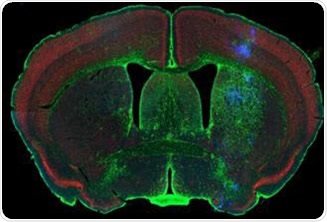

Rodent brain (top) depicting simultaneous acquisition of fluorophores Cy2, Cy3 and Cy5; Brain image (bottom) magnified to 0.5 μm

Figure 1. Rodent brain (top) depicting simultaneous acquisition of fluorophores Cy2, Cy3 and Cy5; Brain image (bottom) magnified to 0.5 μm. Image credit: Huron Digital Pathology.